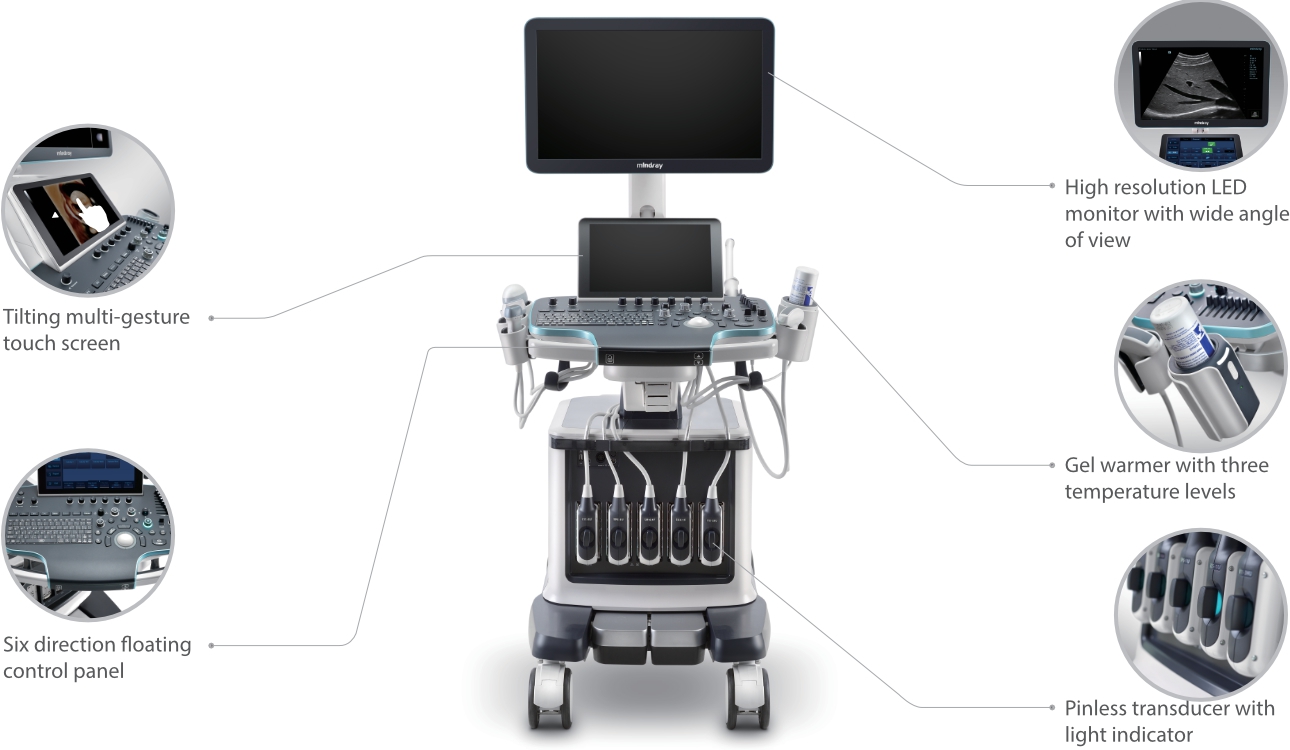

Resona 7

?? ??? ??

Mindray? ??? ??? ?? ??? ???? ??? ?? ??? ??? ????? ??? ????. ?? ???? ZONE Sonography? ??? ???? ?? Resona 7? ??? ZST+ ???? ?? ?? ? ?? ??? ????? ?? ??? ??? ??? ? ?? ????.

?? Resona 7? ???? ??? ?? ???? ??? ??? ???? ??? ?? ???? V Flow? ?? CNS ??? ?? 3D ??? ???? ?? ???? ?? ??? ?? ?? ?? ??? ??????. ???? ??? ??? ?? ?? ??? ??? ?? ?? ??? ??? Resona 7? ??? ???? ???? ??? ??? ??? ????.